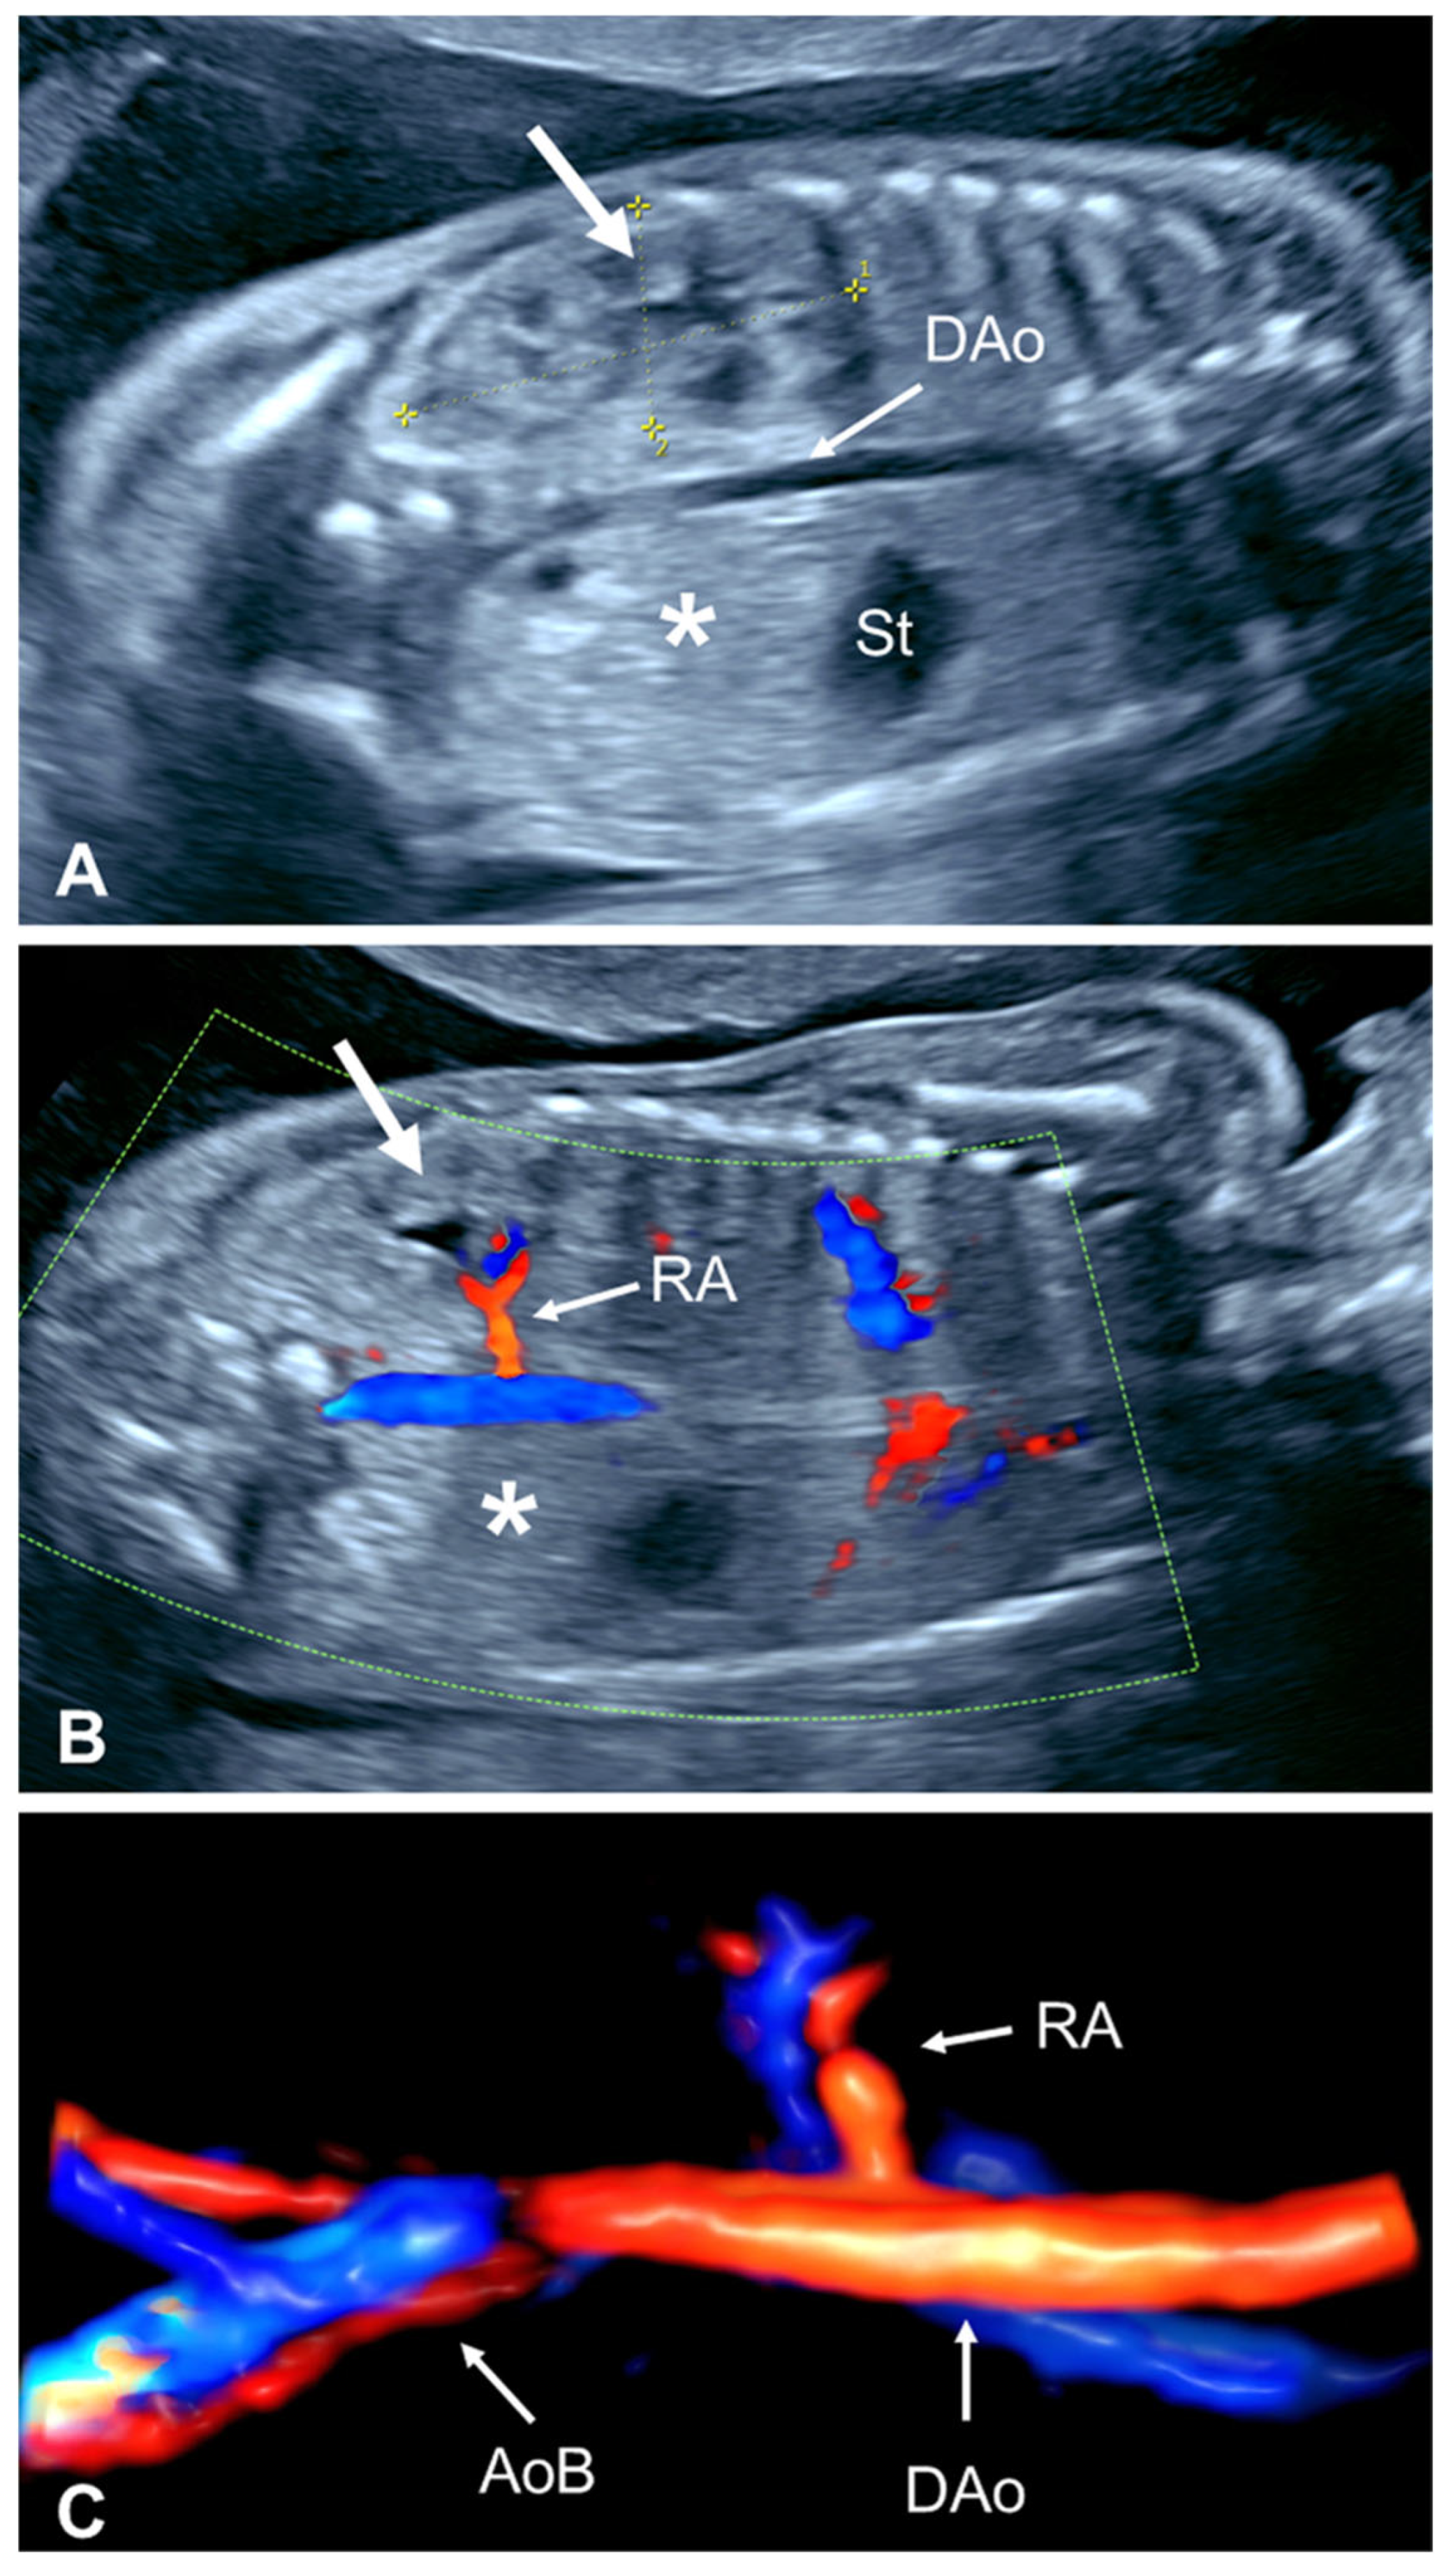

2.2.4. Absent Ipsilateral Renal Artery